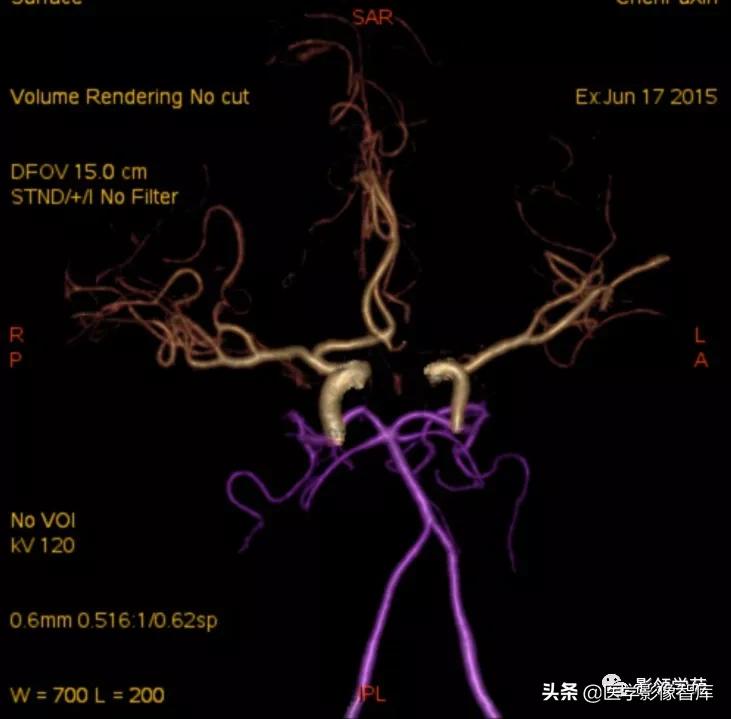

- DSA-金标准、最可靠,但有创,且不能显示完全血栓化的动脉瘤,而CT、MRI则可显示。(CTA、MRA可诊断,尤其是MSCTA具有较高的敏感性和特异性。)

头颅CTA:基底动脉起始部血管局部瘤样突起(宽基底),无占位效应。